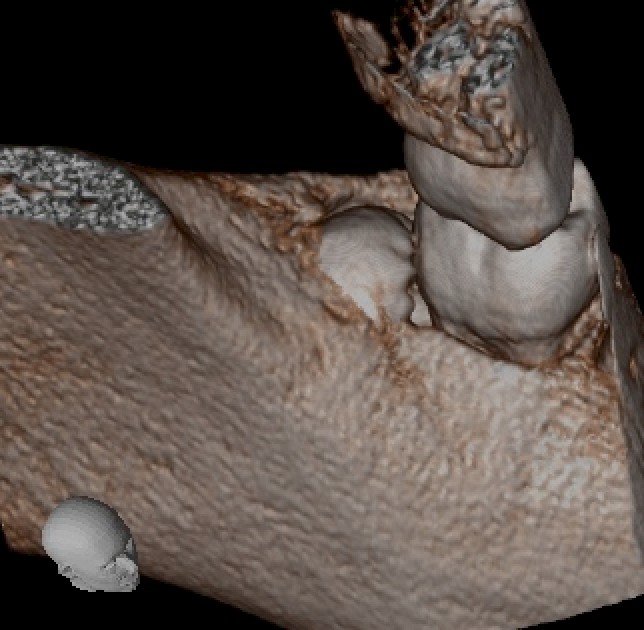

歯根形態

歯根はこのように明確に2根存在し、やや末広がり(開大)した形態をしています。

末広がりした歯根は歯槽骨に引っかかりやすく、一塊のままでは抜去できないことがほとんどです。

そのため、歯根を分割して抜歯するという判断が必要になります。

3Dイメージ

3D画像では、歯冠の一部がわずかに見えていますが、ほとんどが歯槽骨に覆われていることがわかります。

このような場合、歯冠を取り出すためには、歯冠を露出させる必要があり、骨を一部削合する処置が必要となります。